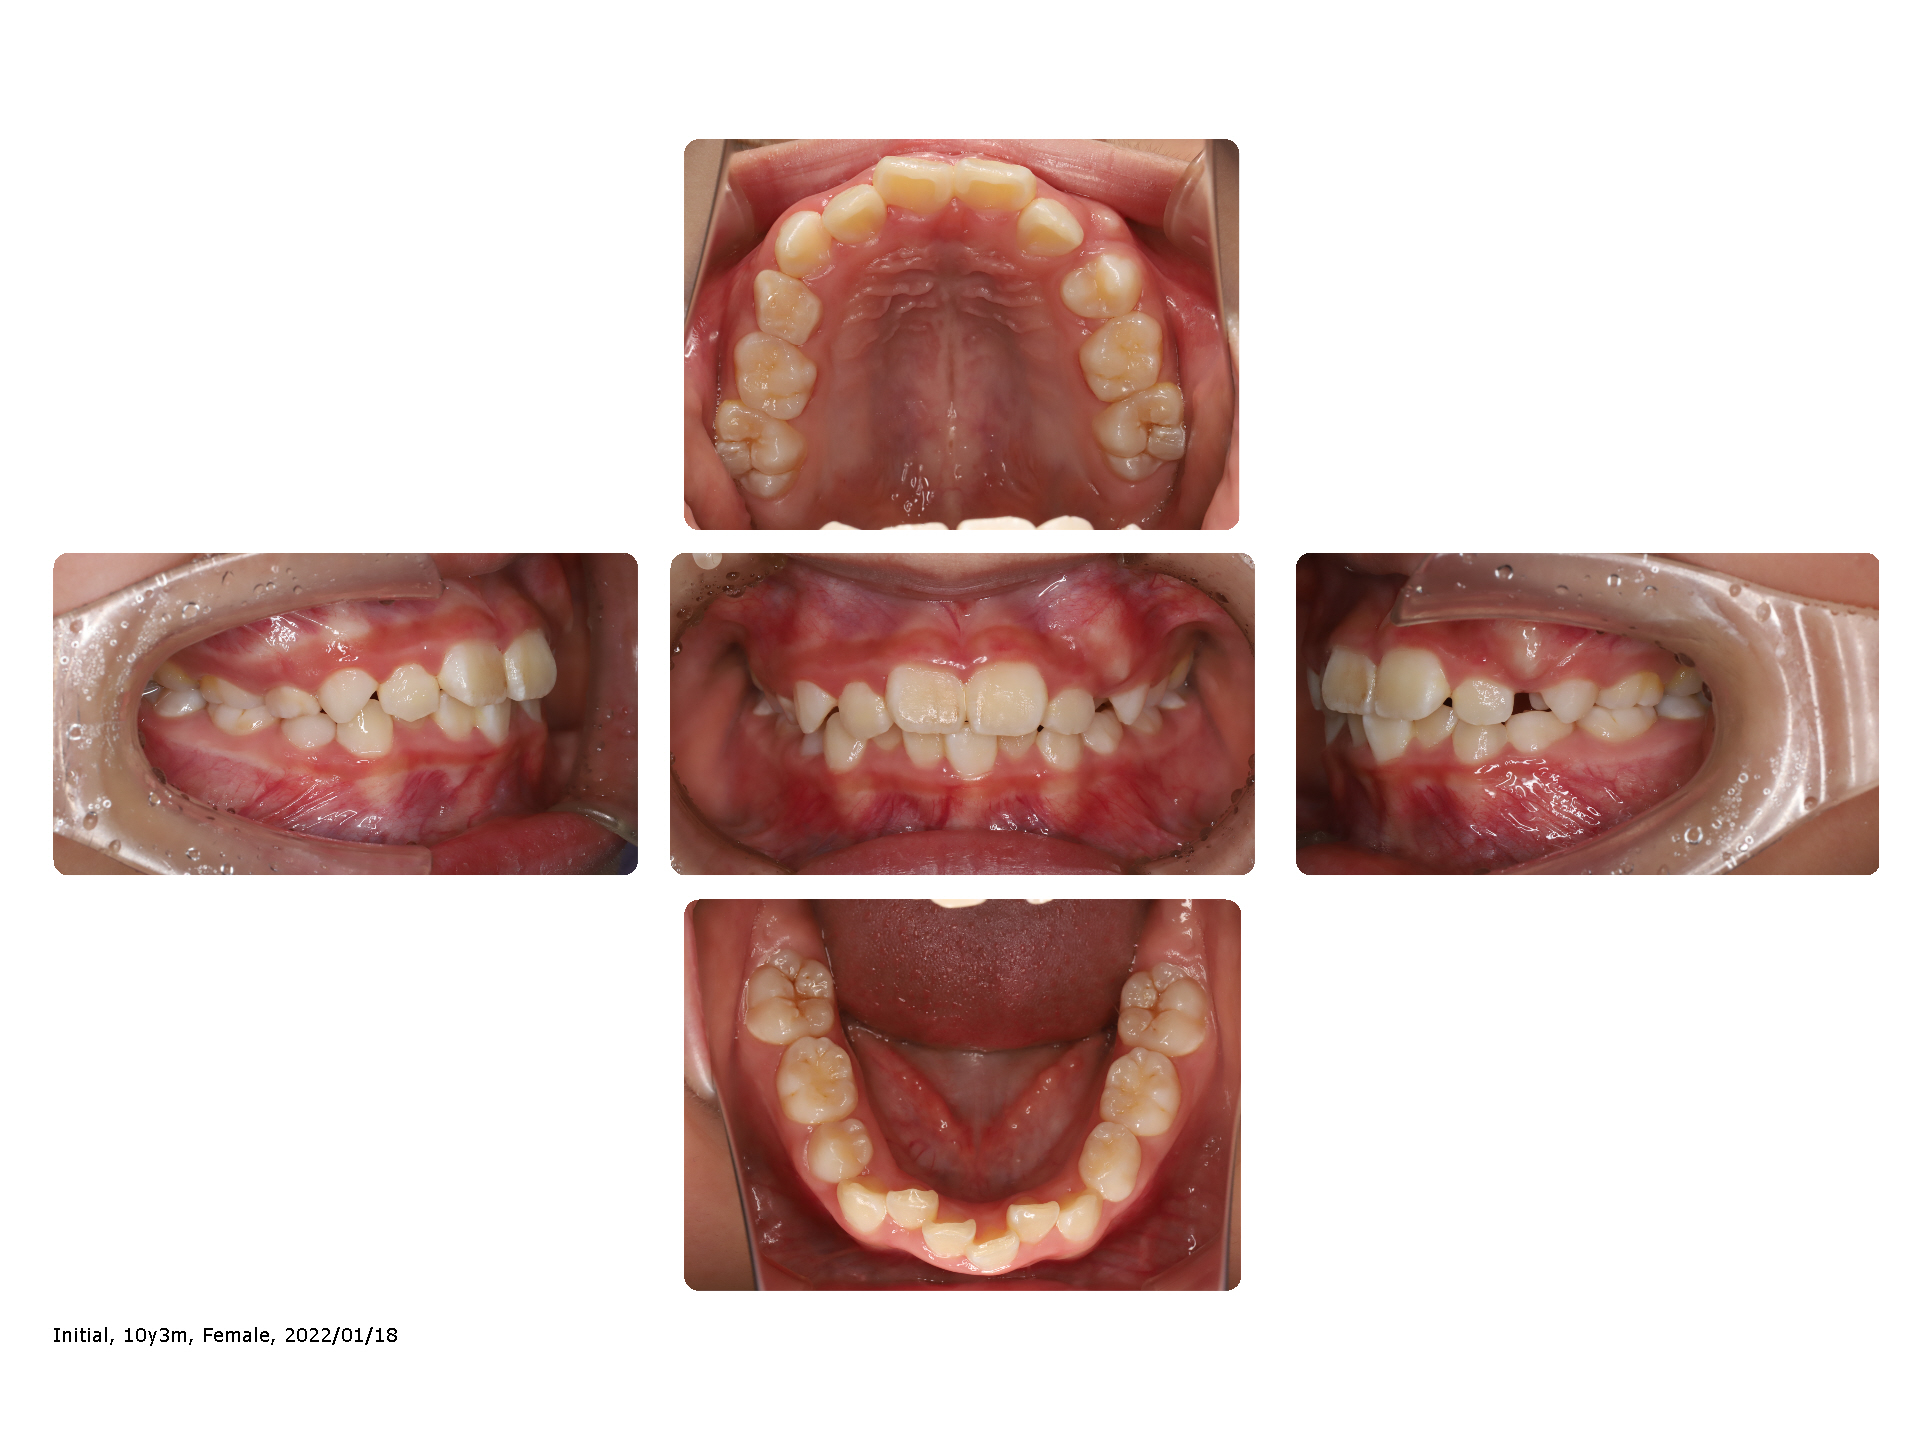

叢生

萌出スペースが不足している場合、前歯が内側に出てきたり斜めに生えることがあります。

歯列の幅を無理のない範囲で広げる(拡大する)ことで、萌出するための場所を確保出来る場合があります。

広げた場所にズレている歯を誘導することで、整えることが可能となります。

歯の萌出と、装置を使用するタイミングが、治療効果には重要な要素と言えます。